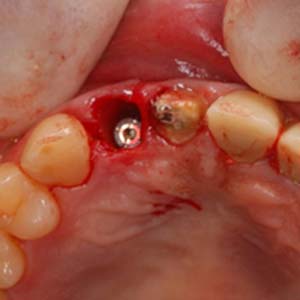

拔除殘留牙根

測量角度與深度

置入適當位置

骨缺損處,置放骨粉

當日在拔除牙齒後,立即在拔牙窩洞裡,置入適當尺寸的植體,並在使用人工骨粉填塞縫隙。